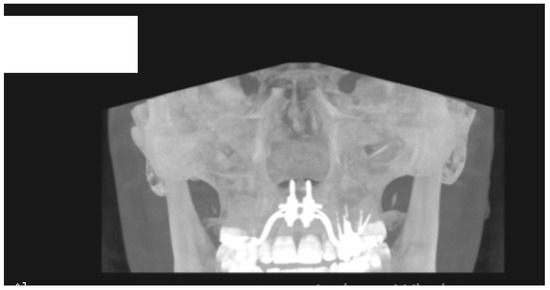

- MARPE associated with cortico-puncture therapy efficiently split the midpalatal suture in adults. The mean split at the anterior nasal spine (ANS) and posterior nasal spine (PNS) was 3.76 and 3.12 mm, respectively. The magnitude of the split at the PNS was smaller than at the ANS (by approximately 85% of the distance), showing that the opening of the midpalatal suture was almost parallel in the anteroposterior direction.

- MARPE therapy associated with cortico-puncture therapy had a positive outcome on midpalatal suture opening and maxillary advancement, but a medium molar inclination of 2.005° was also observed, suggesting that tooth movement cannot be avoided because of the anchorage of the MARPE device at the molar level.

- Our results suggest that non-surgical palatal expansion, assisted by micro-implants and cortico-puncture, is achievable and predictable in young adults. This occurs in safe conditions without the need for more complex surgical treatment.

- The combination of MARPE and the cortico-puncture method proved to be a non-surgical treatment option to correct maxillary transverse deficiency in young adult patients. Cortico-puncture was able to weaken the suture interdigitation, thus facilitating the split.